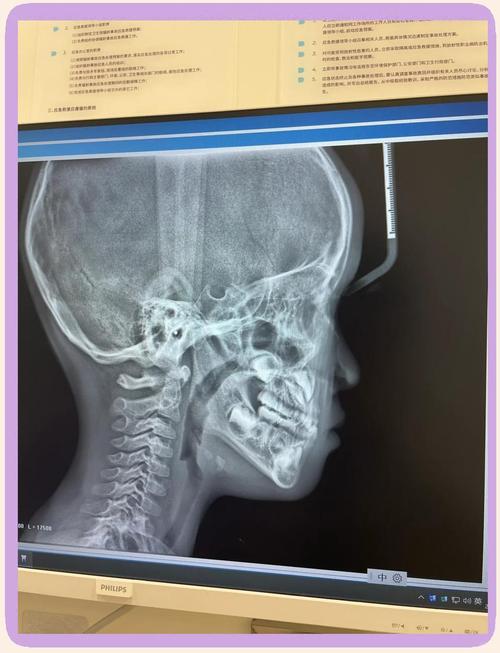

值得注意的是,正畸干预需严格遵循“个体化”原则,避免过度干预,在儿童期盲目扩弓可能导致腭中缝早闭,影响颅底发育;青春生长高峰期过度抑制下颌生长可能造成关节紊乱,治疗前需通过X线头影测量(评估骨骼形态、生长方向)、曲面断层片(观察牙齿发育)、手腕骨龄片(判断生长潜力)等检查,综合制定方案,治疗后长期随访(至少2年)同样重要,以观察复发风险(如牙齿移动回原位、颌骨生长未达预期)并及时处理。